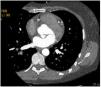

The echocardiogram subsequently performed showed a left aorto-atrial fistula located 3 mm from the aortic annulus in the non-coronary sinus next to the left commissure, aortic insufficiency grade 2/4, with valve gradient between 5-6 mmHg and pericardial effusion of 6 mm without hemodynamic compromise. Additionally, with reference to preserved global systolic function (50%), the exam revealed no dilatation of the right cavities (RA-RV gradient 20 mmHg), with mitral Doppler flow type III. Due to evidence of double contour imaging of the aortic wall, a computed tomography angiogram was performed which identified a type A aortic dissection and dissection of the celiac trunk extending to the common hepatic artery (Figure 4). The patient was then transferred to Grenoble Hospital Center, where she underwent surgery with placement of an aorto-aortic prosthesis, aortic valve replacement with a Carpentier bioprosthesis, and fistula closure. The echocardiogram performed after surgery confirmed good global systolic function, a small periprosthetic leak, and minimal mitral insufficiency, with no dilatation of the right cavities.